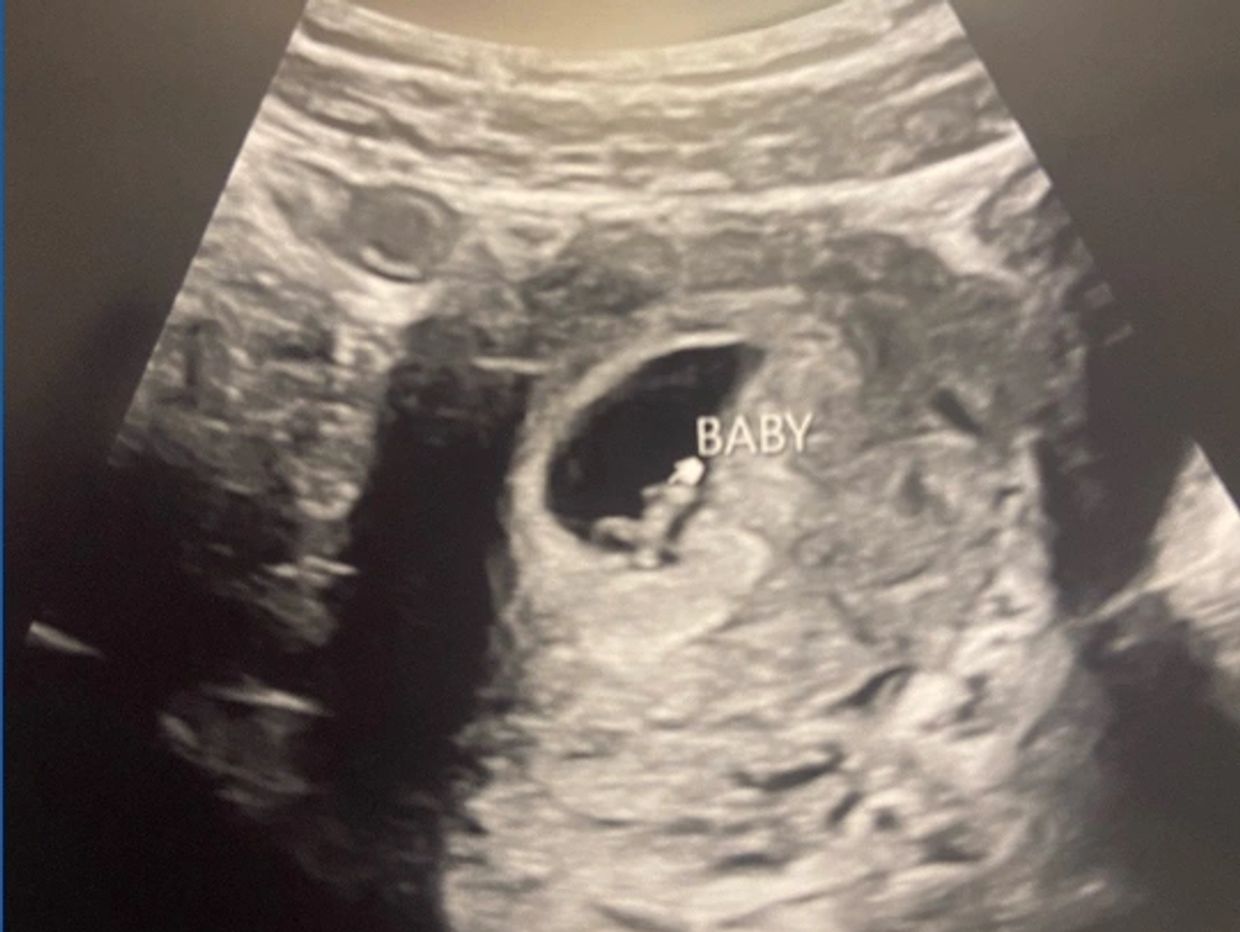

March 28: HEARTBEAT DAY!!! Oh, man. I am so nervous. But also at peace. Does that even make sense? I guess I always say I trust God. So this is a test of that. Either you trust Him, or you don’t. I do. But the natural human in me is anxious and nervous, and excited. Joe and I pulled up to the Lee County Medical Center. That has to be a good sign.

We were greeted by an ultrasound technician that was…well…not very friendly. She was pretty business-like and abrasive. I went to pull down my pants, and she said, “nope, it's stomach.” I said, "oh, ok, sorry." She did the ultrasound on my belly and said, “there is your baby.” I asked well is it moving?? She zoomed in and said, “see it beating?”

It was beating!! You could see it clearly!! We were so excited. Joe tried to videotape, but she quickly said, “no videos allowed!” Haha, of course, she did. Tears rolled down my cheek. I think they were tears of relief more than anything. Joe is smiling. He said he knew it would work this time all along. This is a great first step. A long way to go, but what a blessing.